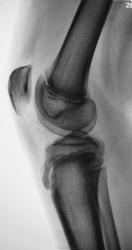

Пациент хирургом направлен на рентгенографию коленного сустава.

норма

Полагаю, болезнь Шляттера. Хотелось бы сравнить со здоровой конечностью.